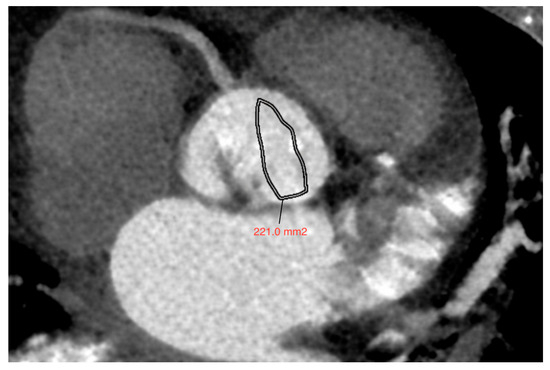

Aortic Valve Calcium Scoring Using True and Virtual Non-Contrast Reconstructions on Photon-Counting CT with Differing Slice Increments: Impact on Calcium Severity Classifications

Background/Objectives: Aortic valve calcification is commonly evaluated using 3.0 mm true non-contrast (TNC) computed tomography (CT) images. This study evaluates the reproducibility of virtual non-contrast (VNC) reconstructions at different slice intervals using photon-counting detector CT (PCD-CT). Methods: In this retrospective study, [...] Read more.

Background/Objectives: Aortic valve calcification is commonly evaluated using 3.0 mm true non-contrast (TNC) computed tomography (CT) images. This study evaluates the reproducibility of virtual non-contrast (VNC) reconstructions at different slice intervals using photon-counting detector CT (PCD-CT). Methods: In this retrospective study, we included 279 consecutive patients, who underwent PCD-CT for evaluation of native aortic valve between February 2023 and December 2023 with both TNC and VNC images at 3.0 and 1.5 mm slice intervals. Aortic valve calcium score (AVCS) and aortic valve calcium volume (AVCV) were compared between the two methods using paired t-tests. Agreement for continuous variables was assessed using inter-class coefficients (ICCs). Cohen’s Kappa (κ) was calculated to evaluate the agreement between different modalities in diagnosing severe AV calcification. Results: Compared to the standard, TNC images at 1.5 mm intervals showed higher AVCS (mean difference: −290 ± 418, p < 0.001), with high reproducibility between techniques (CS: ICC 0.969, [IQR 0.962, 0.975]). Compared with reference, VNC showed no significant differences in AVCS at either slice intervals, with excellent reproducibility (3.0 mm, ICC 0.970 [0.963, 0.976]; 1.5 mm, ICC 0.971 [0.964, 0.977]). Compared to TNC 3.0 mm, strong concordance was observed using other reconstruction techniques in assessing severe AV calcification (κ = 0.81 [95% CI: 0.74–0.88], 0.83 [95% CI: 0.76–0.90], and 0.83 [95% CI: 0.76–0.90] for TNC at 1.5 mm, VNC at 3.0 mm, and 1.5 mm, respectively), with low misclassification rates. Conclusions: Our study highlights high reproducibility in the evaluation of AVCS by VNC reconstruction at 3.0 and 1.5 mm intervals compared with reference offering a reliable alternative with an excellent diagnostic accuracy. Full article

(This article belongs to the Section Cardiovascular Imaging)

Show Figures

Figure 1